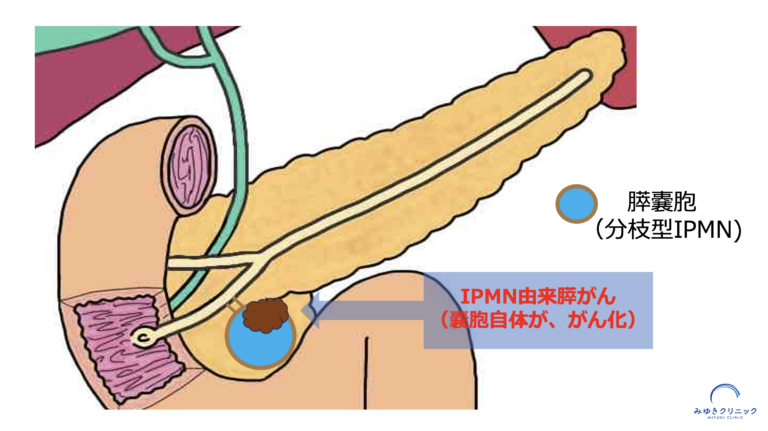

IPMNに関連する膵がんには、

IPMNそのものががん化するタイプ(IPMN由来膵がん)と、

IPMNとは別の場所に発生するタイプ(IPMN併存膵がん)の2種類があります - 特にIPMN併存膵がんは、嚢胞の大きさに関係なく発生することがあります

IPMNが徐々に変化し、膵がんへ進行する「IPMN由来膵がん」

ひとつは、IPMNそのものががんへ進行する「IPMN由来膵がん」です。